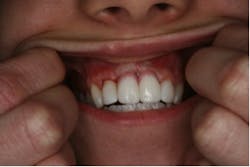

The patient, a 13-year-old female, was seen for emergency treatment in July 2005. The child was catapulted over the handlebars of a bicycle, resulting in the avulsion of the right and left permanent maxillary central incisors. The avulsed teeth were left dry in the palm of her hand for 10 minutes until she reached the hospital where the teeth were placed in milk. Other oral injuries included a laceration on the right side of the philtrum, which was sutured. Examination of the avulsed teeth revealed that the crowns were intact but the mesial incisal edges of both were fractured. Treatment options were explained to the parents and replantation of the avulsed teeth was chosen. She was referred to a local dentist to have the teeth replanted. The roots of the teeth were planed to remove any debris and were then reinserted into the alveolar socket and secured with a splint for six weeks. During the next year the patient had root canals done, followed by metal posts and PFM crowns placed on the avulsed teeth (Figure 1).

Due to the patient’s age at the time of trauma, the crowns were replaced five years later with lava crowns, which are porcelain crowns with a zirconia framework inside (refer to figure 2a and 2b).